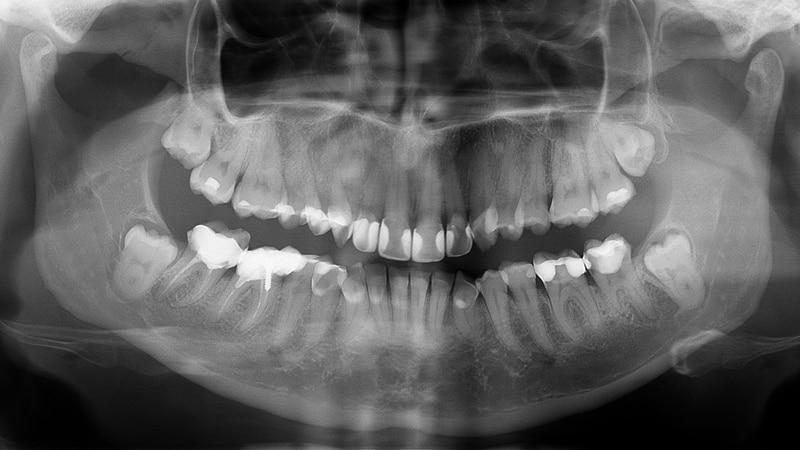

Диагностику данного заболевания проводит стоматолог. В первую очередь, врач осматривает ротовую полость с помощью зонда и стоматологического зеркала. Этот визуальный осмотр позволяет обнаружить темные пятна на боковых поверхностях эмали, которые пациент мог не заметить. Если повреждения слишком мелкие или расположены в труднодоступных местах, может потребоваться рентгенография. Этот метод является надежным способом для выявления кариозных полостей между соседними зубами. В случаях, когда рентгенография противопоказана, стоматолог может воспользоваться фотополимеризатором – устройством, которое освещает костную ткань мощным светом, позволяя выявить скрытый кариес или его начальные стадии.

Во время осмотра стоматолог проводит тщательную проверку состояния зубов и десен, используя специальные инструменты и технологии, такие как рентгенография. Это помогает обнаружить кариес, который может быть незаметен при обычном осмотре, особенно в труднодоступных местах между зубами. Раннее выявление кариеса позволяет избежать более серьезных проблем, таких как пульпит или абсцесс, которые требуют более сложного и дорогостоящего лечения.